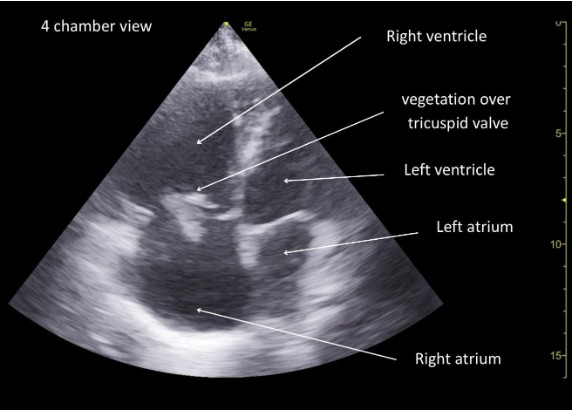

A bedside POCUS SUPER protocol (Sepsis Ultrasound Protocol to identify source Etiology Rapidly) was performed during early resuscitation. The full protocol will be described in the discussion section and Figure 1. In this patient’s case, focused cardiac ultrasound demonstrated a mobile echogenic mass attached to the tricuspid valve, suggestive of infective endocarditis. (Figure 2). Three sets of blood cultures were obtained, and antimicrobial therapy was promptly tailored toward catheter-related bloodstream infection. Subsequent investigations confirmed right-sided infective endocarditis, and early ultrasound-based source identification facilitated timely, targeted management.

Figure 2: Focused cardiac ultrasound (4 chamber view) demonstrating a mobile echogenic mass attached to tricuspid valve suggestive of infective endocarditis.